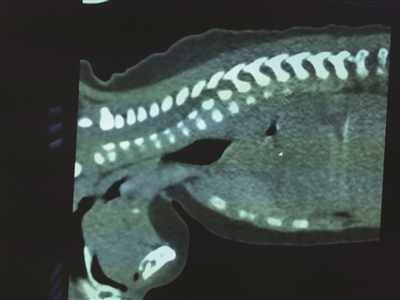

厦门4岁男孩莫名呕吐两次后身亡 生前哭着找爸